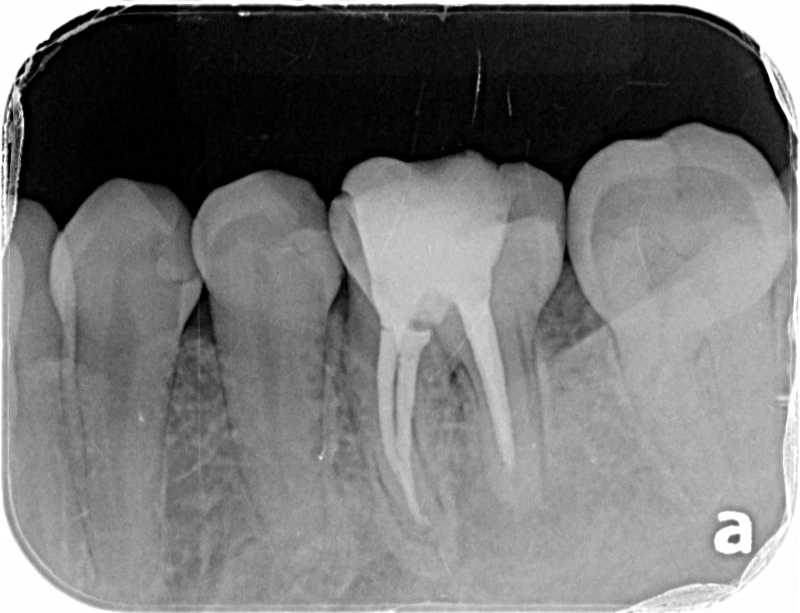

左下第一大臼歯が腫れて痛いということで来院されました。 レントゲンおよびCT撮影をしたところ、根っこの先および周囲が黒く抜けており、膿が溜まっている状態でした。 術後のレントゲンおよびCTで黒い影が小さくなっていることを確認し、ファイバーコアによって土台を作り、セラミッククラウンによる被せ物を装着致しました。 |

術前のCTになります。歯根の周囲が黒く抜けており、膿が溜まっております。

術後のCTです。黒い部分が小さくなってきており、骨が再生されてきているのが確認できます。